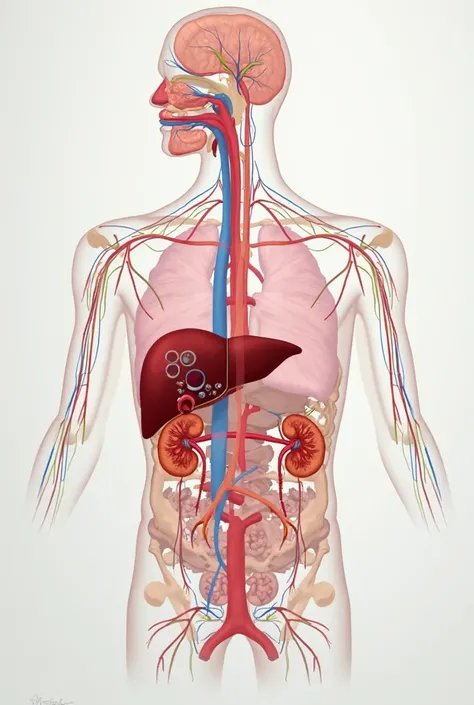

A diagram of the anatomy of the human body